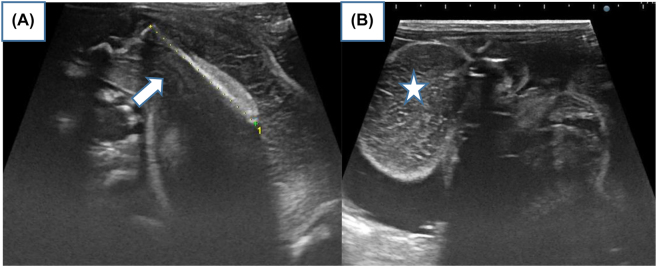

Objectives: Fetus-in-fetu is a rare congenital anomaly that occur secondary to abnormal embryogenesis in a diamniotic monochorionic pregnancy. Its diagnosis can be accurately made by imaging ultrasonography, radiography, computed tomography, or magnetic resonance imaging. Differential diagnosis is an important issue because FIF, teratoma and cystic meconium peritonitis are very different in terms of their respective disease courses.

Case presentation: This is an interesting rare case of a 22-year-old pregnancy woman, presented for a routine antenatal ultrasound. The diagnosis of a fetus-in-fetu was suspected, complete surgical excision of the lesion was performed and the diagnosis was histopathologically confirmed.

Conclusions: We describe also the common characteristic of FIF as revealed by prenatal and postnatal US, postnatal MRI, and the operative findings.